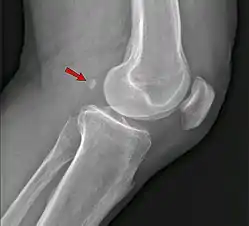

An accessory bone or supernumerary bone is a bone that is not normally present in the body, but can be found as a variant in a significant number of people. It poses a risk of being misdiagnosed as bone fractures on radiography.[2]

The os ulnostyloideum is an ulnar styloid process that is not fused to the rest of the ulna bone.[6] On X-rays, an os ulnostyloideum is sometimes mistaken for an avulsion fracture of the styloid process. However, the distinction between these is extremely difficult.[6][7] It is alleged that the os ulnostyloideum has a close relationship with or is synonymous with the os triquetrum secundarium.[8]